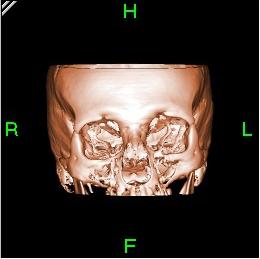

ويستعمل الأطباء فحوص التصوير المقطعي الحاسوبي لتشخيص كثير من الحالات مثل الأورام والإصابات وتجلطات الدم وكسور العظام. ويساعد التصوير المقطعي الحاسوبي أيضًا في معالجة بعض الأمراض، التي قد تتطلب جراحة بطريقة أخرى. فمثلا،ً يمكن للأطباء استعمال التصوير المقطعي الحاسوبي لإرشادهم إلى إدخال القثطار (أنبوب رفيع) إلى خُرّآج في الجسم لسحب الصديد من المنطقة الملوثّة.

تعود تسميتها إلى كون هذه الطريقة تعطى صورًا شعاعية على شكل مقاطع للجسم، يجري التصوير المقطعي المحوسب بواسطة جهاز خاص، يسمى جهاز التصوير المقطعي المحوسب أو الماسحة المقطعية المحوسبة، تتميز هذه الطريقة بدقتها، تعطي صورًا واضحة، ويمكن أن تعطي صورًا لأماكن قد تكون من الصعب تصويرها بالتصوير الشعاعي التقليدي، كذلك يمكن عملها بشكل سريع ودقيق.

يمكن للأطباء أن ينظروا داخل جسم المريض عن طريق طلب إجراء مسح للعظام والأوعية الدموية والأدمغة والأنسجة الرخوة بفضل ماسح التصوير المقطعي الحاسوبي (CT). بعد إجراء أول فحص طبي بالأشعة المقطعية للمريض في عام 1971، استخدم أطباء الأشعة عمليات المسح لتشخيص الأورام والصدمات والتخطيط للعلاج الطبي والجراحي والإشعاعي في جميع أجزاء جسم الإنسان تقريباً.